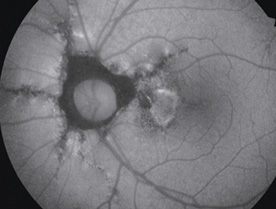

In addition to non-mydriatic color, mydriatic color, fluorescein angiography (FA), Red-free (RF), fundus autofluorescence (FAF*) is added to allow 5 photography modes.

Fluorescein Fundus Angiography (FA)

Photo : Showa University